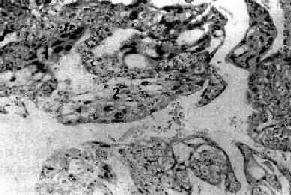

镜下,成片增生及分化不良的滋养层细胞侵入肌层和血管。组织由分化不良的两种滋养层细胞组成,即细胞滋养细胞和合体滋养细胞。细胞滋养细胞胞浆丰富、淡染,细胞境界清楚,核空泡状。合体滋养细胞体积大、胞浆红染并互相融合,核椭圆形。这两种细胞排列紊乱(图13-13)。不同肿中这两种细胞所占比例不同,有的以细胞滋养细胞为主,有的以合体滋养细胞为主。核分裂像常见。绒组织无间质,常呈广泛出血坏死,不形成绒毛结构。如发现有绒毛,即使是退化的绒毛,也应诊断为侵蚀性葡萄胎。

图13-13 绒毛膜

组织没有间质,巢由于两种细胞组成:1.合体细胞样细胞;2.细胞滋养层细胞样细胞